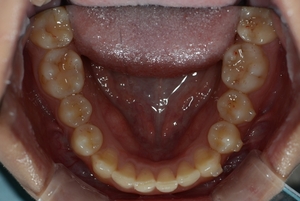

ガタガタとした歯並びや八重歯(叢生)CASE65